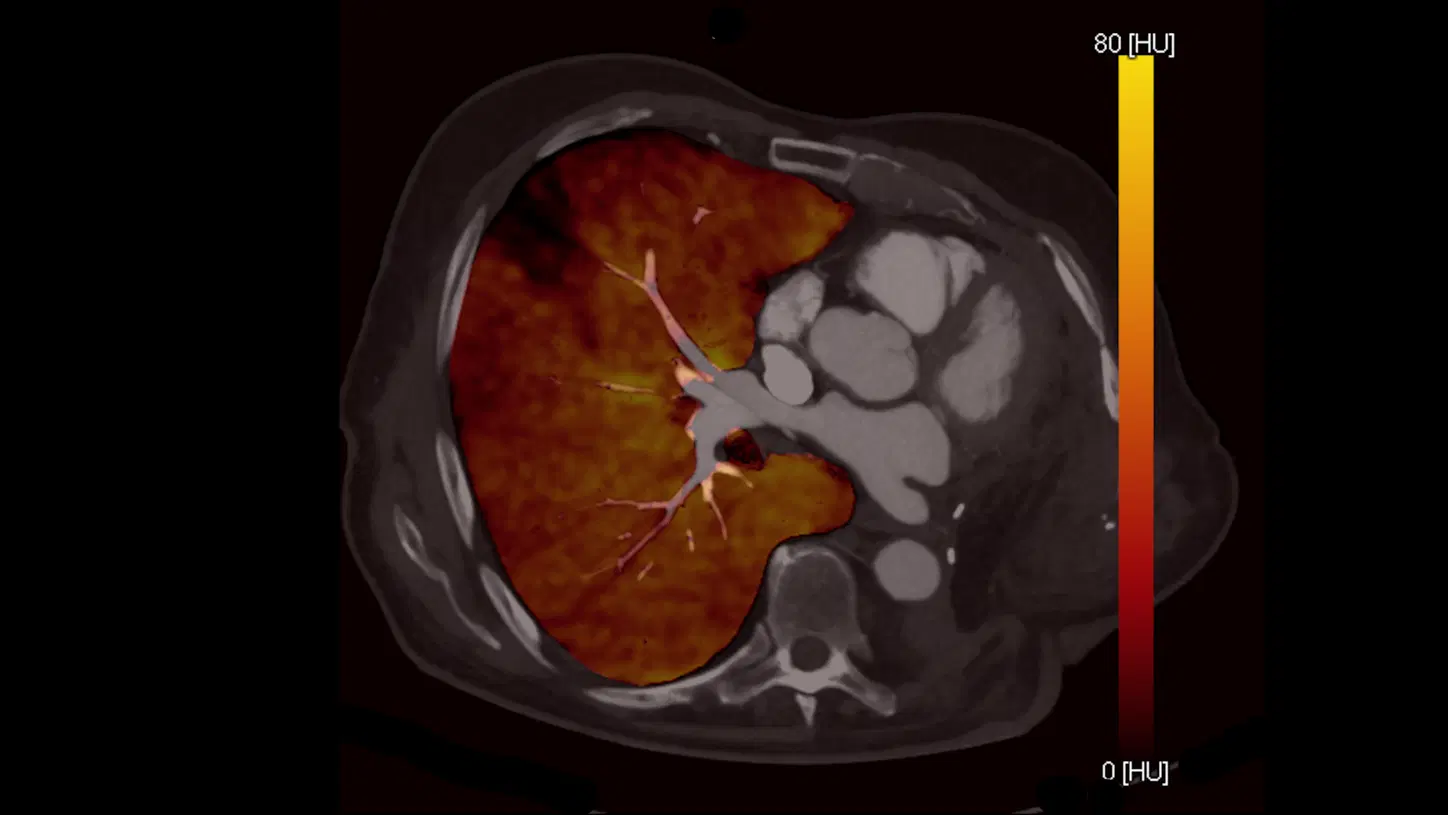

Tomografia Espectral

Spectral CT Imaging

Imagem de TC Espectral com diferenciação de materiais. Fonte: Wikimedia Commons

A Tomografia Espectral, também conhecida como Dual-Energy CT, utiliza dois espectros de energia de raios X para diferenciar materiais com base em suas características de atenuação.

• Tecnologia: Pode ser baseada em fontes (ex.: alternância de kV) ou detectores (ex.: Philips Spectral CT), capturando informações espectrais em uma única varredura.

• Benefícios:

• Diferenciação de materiais, como iodo, cálcio e gordura.

• Geração de imagens virtuais sem contraste (virtual non-contrast).

• Realce de materiais específicos, como iodo em imagens vasculares.

• Aplicações Clínicas: Oncologia (caracterização de tumores), imagem vascular (otimização de contraste) e caracterização tecidual.

• Estado Atual: Sistemas como o Philips Spectral CT e o GE GSI Xtream são amplamente utilizados, com eventos educacionais como o Spectral CT Masterclass 2025 destacando sua relevância.